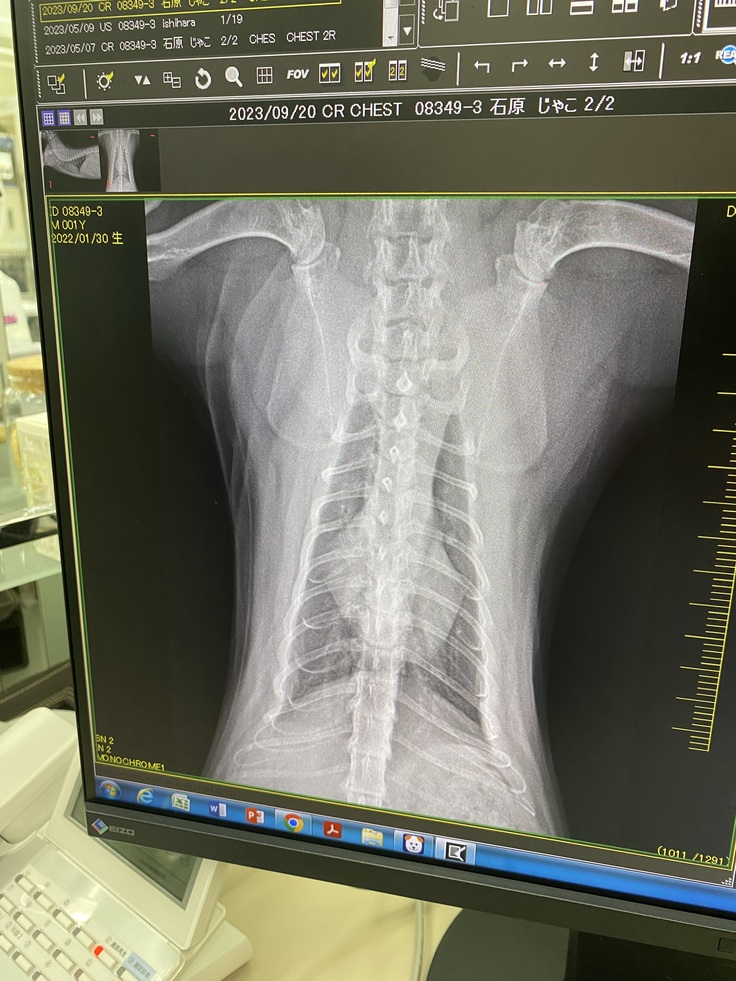

↓レントゲン(9/20)

1週間で数値は改善しました。

AG比も発症時0.36→1.06へと上がりました。